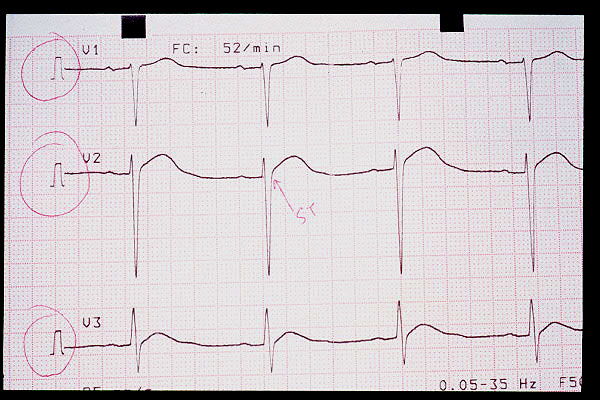

ECG

Espiga de marcapasos y bloqueo de rama.